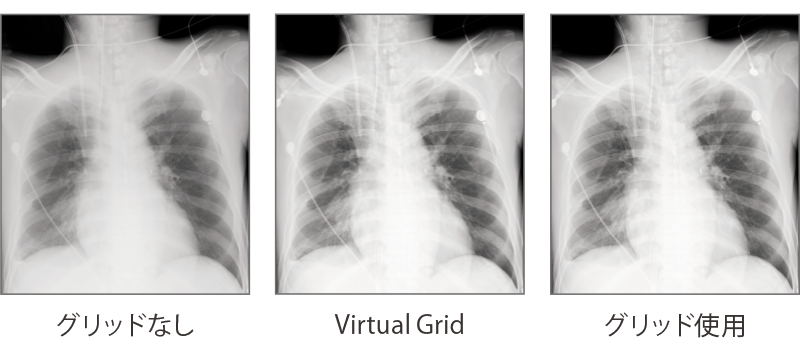

撮影条件(X線の強さ、量など) や撮影部位、被験者の体格などさまざまな要因の影響を受ける散乱線成分を高速かつ忠実に算出。散乱線によるノイズを抑制し、コントラストを調整しています。(オプション)